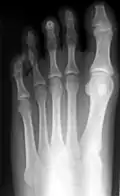

Röntgenbilder

Hammerzehen vor einer operativen Korrektur -

Hammerzehen nach der operativen Korrektur; deutlich sind die verkürzten dritten Glieder der drei inneren Zehen erkennbar (Operation nach Hohmann). Bei dieser OP wurde auch der Hallux valgus korrigiert. -